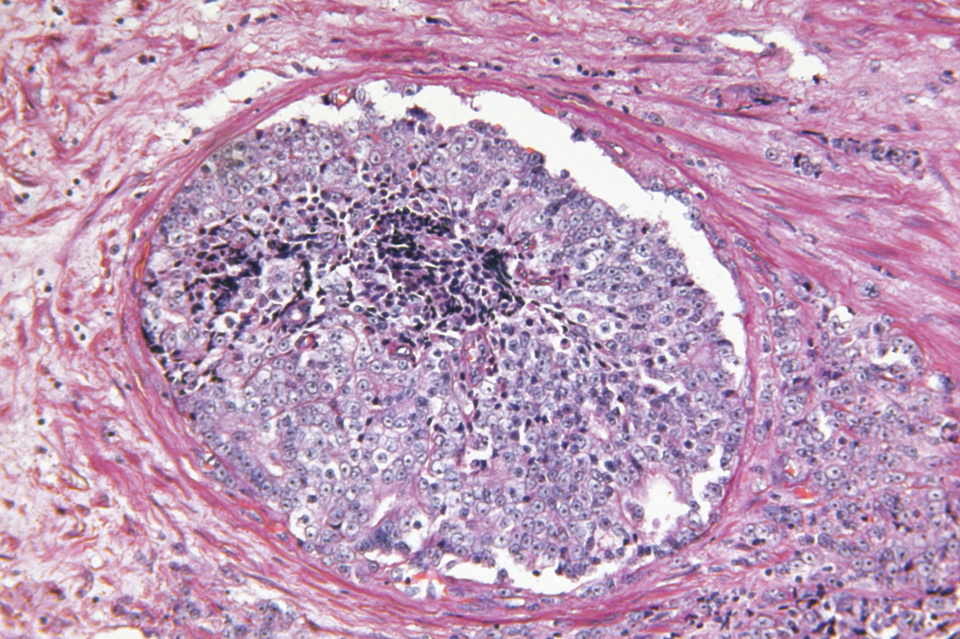

Befund eines Prostatakarzinoms Befund eines Prostatakarzinoms © iStock/BeholdingEye